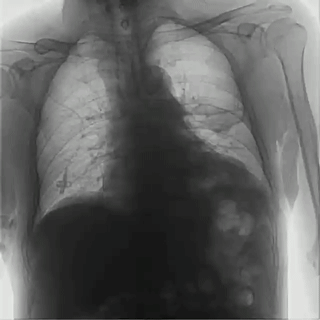

首先,具有可視化操作的功能,能通過(guò)多角度動(dòng)態(tài)影像觀察,瞬時(shí)高清點(diǎn)片,更好地發(fā)現(xiàn)病灶并進(jìn)行相關(guān)疾病的治療,解決了常規(guī)靜態(tài)DR不能解決的問(wèn)題,減少漏診誤診,提高臨床診斷的精準(zhǔn)性。

其次,臨床應(yīng)用更加廣泛,能為影像科提供全科解決方案,針對(duì)體檢科、內(nèi)科、外科、骨科、急診科等也能提供相應(yīng)的解決方案,且檢查更精準(zhǔn)、直觀,擺位攝片效率極大地提升,大大節(jié)省拍片時(shí)間。